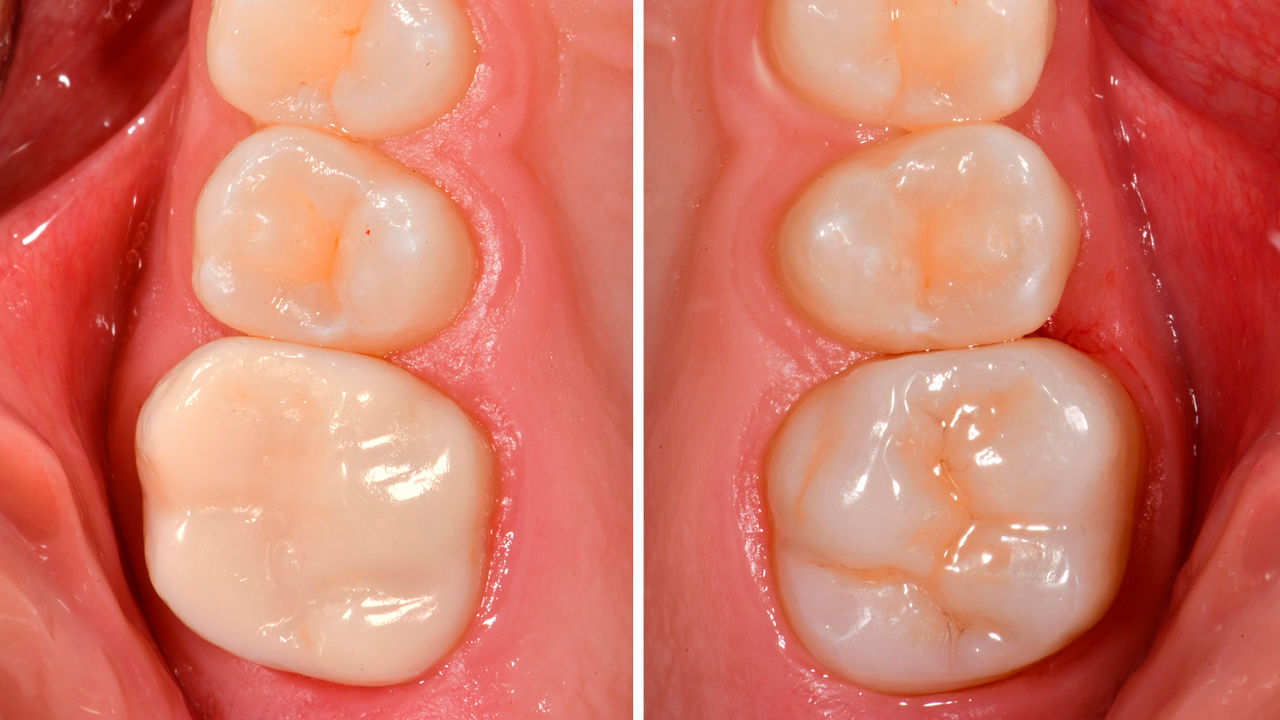

Before: Insufficient fillings in the second quadrant. The restorations were about 15 years old.

After: Chairside-fabricated crowns made from CEREC Tessera (teeth 26/27). Inlays for teeth 24 and 25 made of composite blocks.